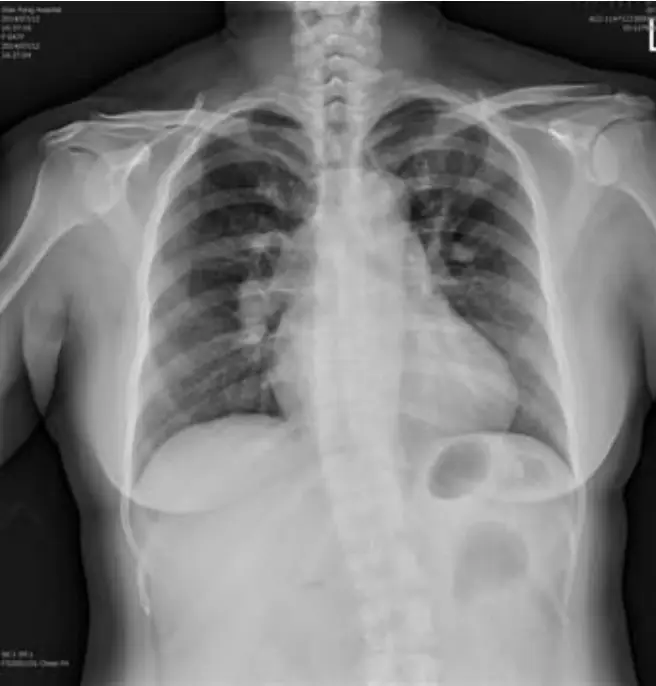

女性病人現年47歲,G2P2,主訴近來一個月間時有頭昏,並有漸進式呼吸困難。住院前四天症狀更形惡化,是乃經急診住加護病房。理學所見: 身高163cm; 體重 67.4kg; BMI = 25.37; 體溫:36.5℃ ;BP(mmHg): 128/60; PR(/min): 104; RR(/min): 24; 臉血蒼白; 心跳快速但正常律動, 在三尖瓣區有Grade 3/6 systolic murmur可聞 ,其他尚無重大異常。其心電圖及胸部X光和Computer tomography如圖。 D-Dimer, 3.56 mg/L;Blood gas:pH,7.534;PaO₂,57 mmHg;PaCO₂,20.9 mmHg;HCO₂ std 22.0 mmol/L;病人住院後隨即靜注大方劑量(Bolus dose) Unfractionated Heparin 3000u 及每小時1000u靜脈輸注。病程中先後進行下列處置: (1)通知心臟科啟動PCI團隊 (2) 查Protein C ,Protein S和anti-thrombin III, 和Anticardiolipin IgG (3)Tumor biomarkers :CEA, CA-199,CA-125,CA-153 (4)Heparin bolus 3000 unitIV stat and then IV pump 6~12 U/kg/hr according to the aPTT (5)Digoxin o.25 mg + 20% glucose in water for IV to control tachycardia 請問下列何組處置才是正確的?

本題考察肺栓塞(pulmonary embolism, PE)的診斷與處置。病人為47歲女性,表現為漸進性呼吸困難、頭暈、臉色蒼白、心搏過速(104次/分),三尖瓣區收縮期雜音(Grade 3/6),D-Dimer顯著升高(3.56 mg/L),血液氣體分析顯示呼吸性鹼中毒合併低氧血症(pH 7.534、 57 mmHg、 20.9 mmHg),高度符合急性肺栓塞表現。影像亦支持此診斷。本題核心在於辨別哪些處置是正確且必要的,哪些不適合或反而有害。

圖二(胸部X光): 後前位胸部X光顯示心臟輪廓輕度增大,右下肺動脈幹(right descending pulmonary artery)略有增寬,肺野相對清晰,無明顯肺水腫或肺炎浸潤。右下肺血管紋理稍減少,提示 Westermark sign(